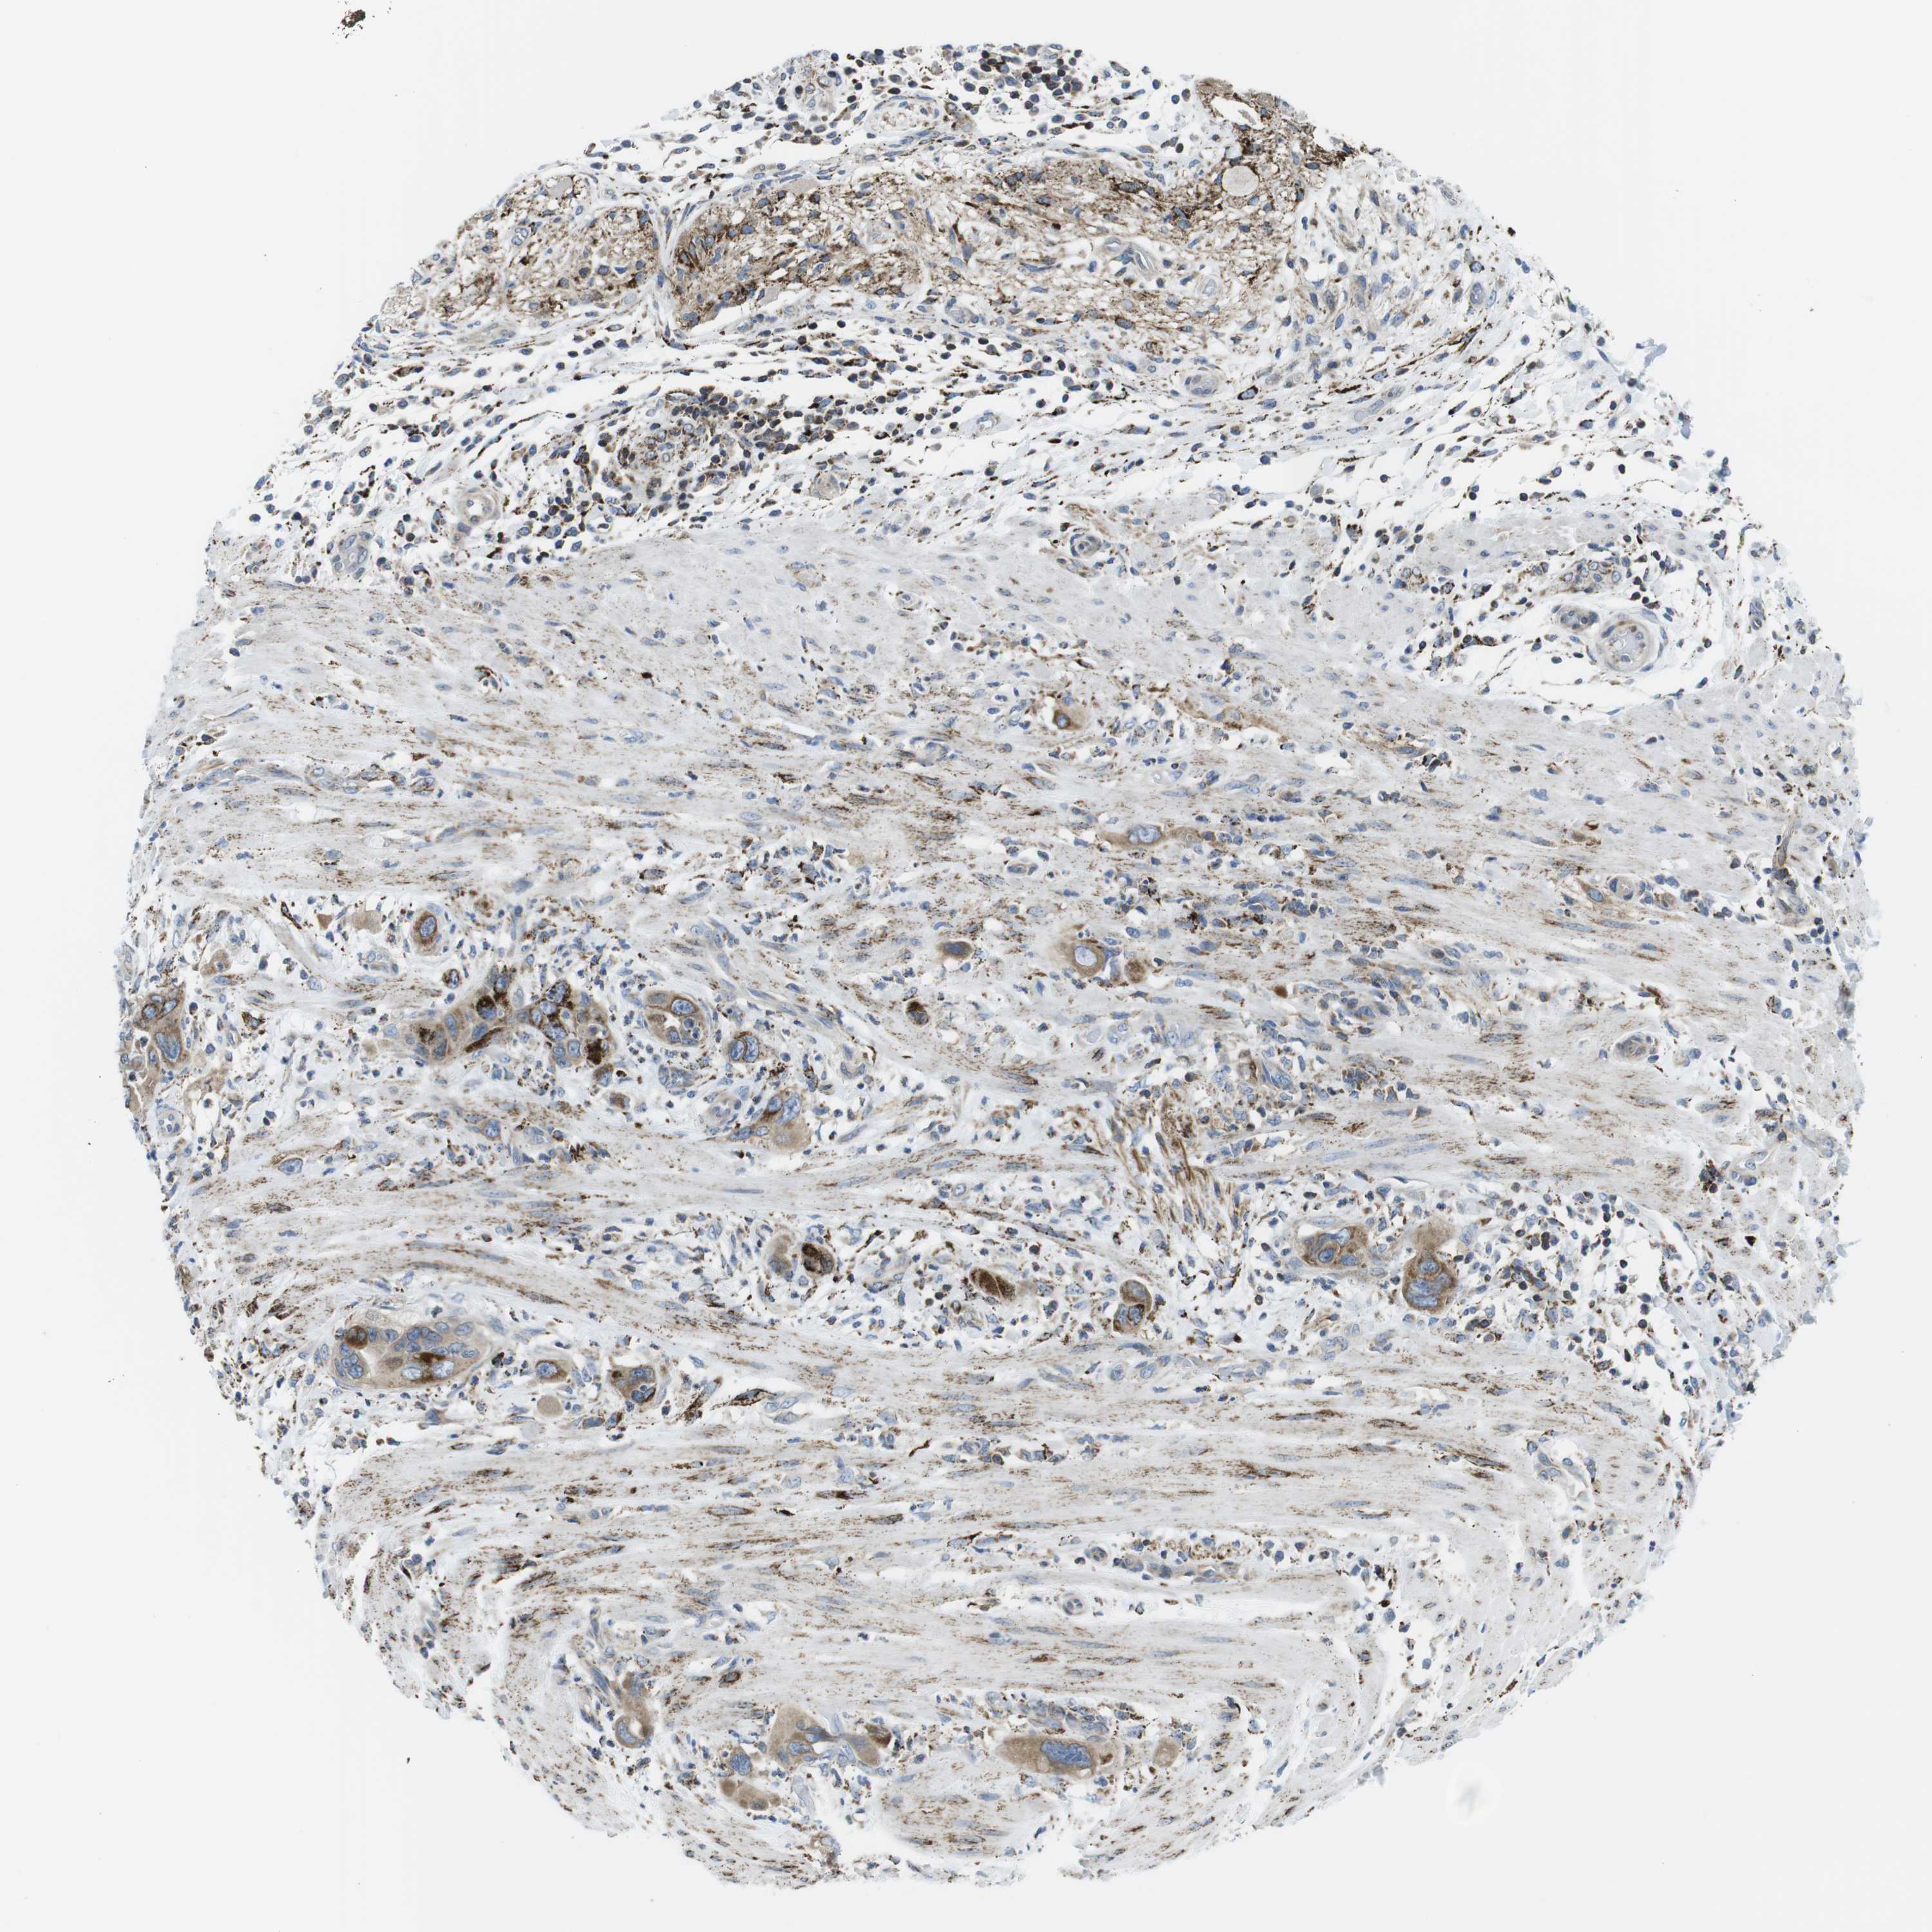

PANCREATIC CANCER - Protein expressioni

A mouse-over function shows sample information and annotation data. Click on an image to view it in a full screen mode. Samples can be filtered based on level of antibody staining by selecting one or several of the following categories: high, medium, low and not detected. The assay and annotation is described here.

Note that samples used for immunohistochemistry by the Human Protein Atlas do not correspond to samples in the TCGA dataset.

Antibody stainingi

Antibody staining in the annotated cell types in the current human tissue is reported as not detected, low, medium, or high, based on conventional immunohistochemistry profiling in selected tissues. This score is based on the combination of the staining intensity and fraction of stained cells.

Each image is clickable and will lead to virtual microscopy that enables deeper exploration of all samples and also displays staining intensity scores, fraction scores and subcellular localization as well as patient and tissue information for each sample.

Antibody HPA014849

Staining

High

Medium

Low

Not detected

Intensity

Strong

Moderate

Weak

Negative

Quantity

>75%

75%-25%

<25%

None

Location

Nuclear

Cytoplasmic/membranous

Cytoplasmic/membranous,nuclear

Adenocarcinoma, NOS